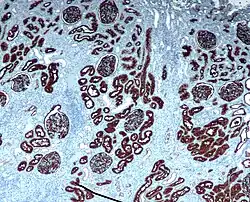

Microscopic cross section of the renal cortex

CD10 immunohistochemical staining of normal kidney. CD10 stains the proximal convoluted tubules and glomeruli. -